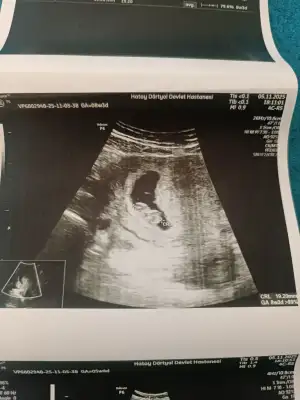

Kizlar hamilelik belirtisi yasamiyordum biliyorsunuz kafamda takılıyordu midemde bulanmiyor sadece midemde gaz sansici vardı bugün doktora gittim doktor 8+3 dedi kalbide çok güzel atıyordu güçlü kalp atışı dedi hiçbir sorun yok haftasıyla uyumlu dedi çok şükür

Cinsiyet belli olurmu kesenin şekline bakarak anlıyorlar ya kizlar yorum yapın bakalım ikinci hamilelik geçiren tecrübeli hamisler😂 8+3 suanki kese

Eklentiler

• IMG_20251105_142205.webp

IMG_20251105_142205.webp

40,7 KB · Görüntüleme: 26